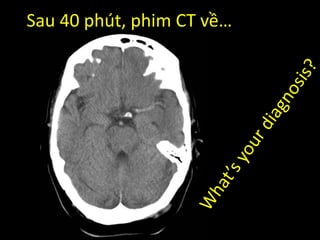

Sau 40 phút, phim CT về…

Nhồi máu động mạch não giữa

bên (T) giờ thứ 4

Mất phân biệt xám – trắng